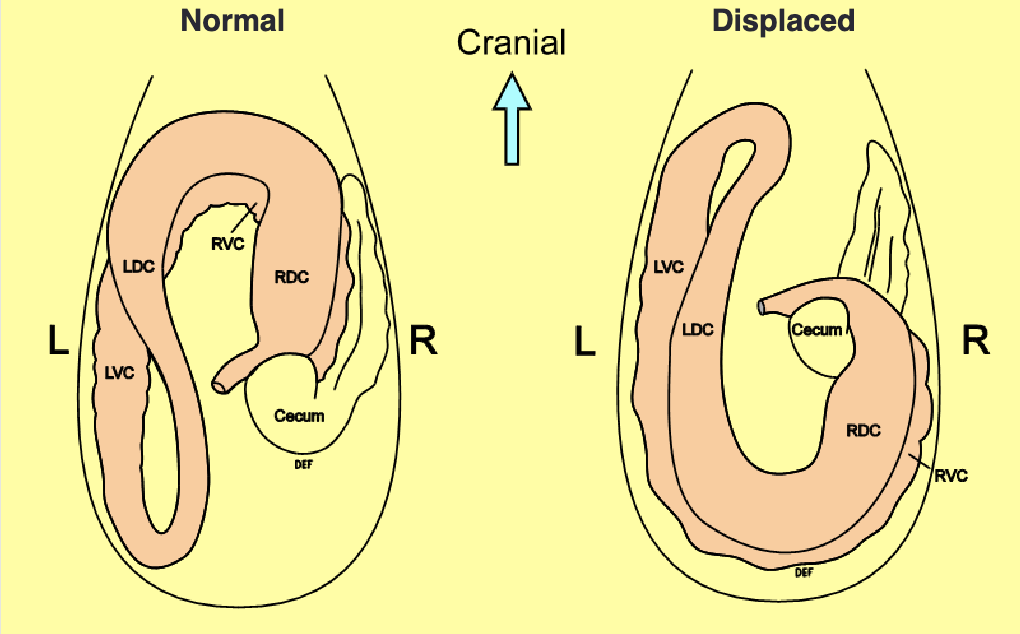

pathway for normal abdomen anatomy

esophagus→stomach→duodenum→jejunum→ileum→cecum(R side, blind ending sac)→right ventral colon→sternal flexure→left ventral colon→pelvic flexure→left dorsal colon→diaphragmatic flexure→right dorsal colon→transverse colon→small colon→rectum

difference btwn dorsal and ventral colons

dorsal= smooth

ventral= has sacculations (bumpy)

left dorsal displacement is aka

nephrosplenic entrapment

right dorsal displacement

pelvic flexure is high and on R side (normally low and L)